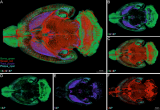

近几年,靶向肿瘤间质FAP的PET/CT显像在全世界范围内的研究方兴未艾。目前报道的显像剂[⁶⁸Ga]FAPI-04在多种肿瘤的治疗前分期及治疗后评估取得令人欣喜的结果,但是[⁶⁸Ga]FAPI-04这类探针存在半衰期短、制备量少等不足,每次的生产的药量少只够1-3病人使用。作为另一种临床上最常用的正电子核素[¹⁸F](109.8分钟)可用回旋加速器大量生产,¹⁸F标记的FAP探针具有合适的半衰期时间,有利于延迟显像以及多个病人检测。 2022-07-05 核医学PET/CT